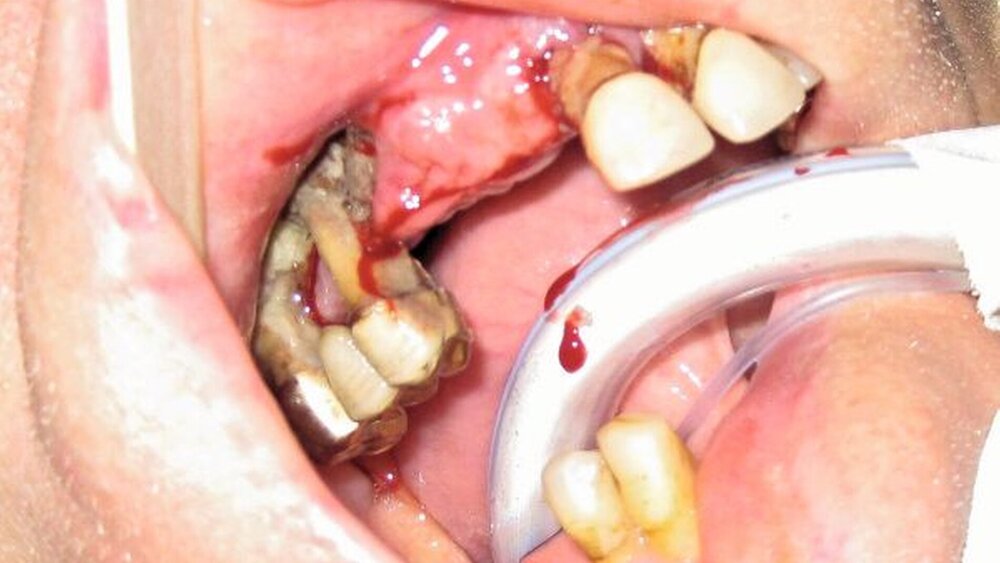

Bei der klinischen Inspektion imponierte ein desolates Gebiss bei starkem Knochenabbau und großflächigem Nekroseareal vestibulär im ersten Quadranten. Die Restbezahnung bestand aus den Zähnen 17, 15, 11 bis 24, 27 sowie 43 und 44. Alle Zähne wiesen Lockerungsgrad III auf. Neben einer spontanen Zahnfleischblutung konnte an mehreren Stellen eine putride Sekretion aus dem Parodontalspalt beobachtet werden. Des Weiteren wies der Patient einen enorm fauligen Foetor ex ore auf.

Als therapeutische Maßnahme erfolgte zunächst unter Intubationsnarkose die Extraktion aller Zähne im Oberkiefer. Hierbei konnte ein großflächiges Knochensequester aus dem ersten Quadranten in toto geborgen werden. Die rechte Kieferhöhle erschien dadurch breitflächig eröffnet, es erfolgte eine ausgiebige Ausräumung des Granulationsgewebes und die Einlage einer Furacintamponade mit Ausleitung zum unteren Nasengang. Der noch verbleibende Alveolarfortsatz des Oberkiefers wurde großflächig dekortiziert, bis sich eine Blutung aus dem Knochen zeigte. Die Deckung erfolgte dann lokal mit Mukoperiostlappen.